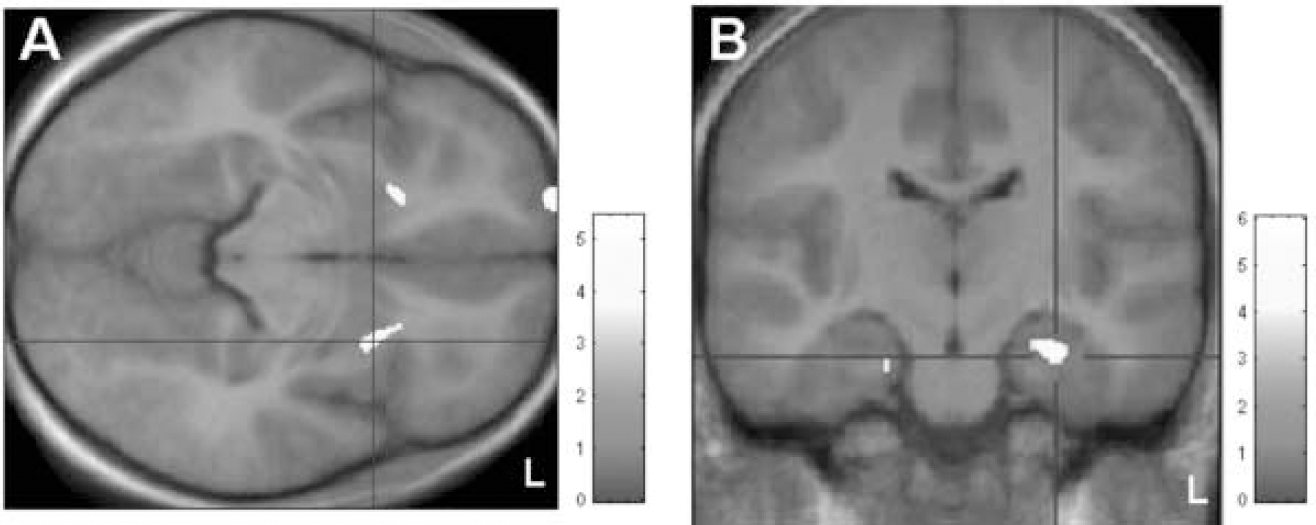

In the optimised voxel-based morphometry analysis, both contrasts ‘patients>controls’ and ‘controls>patients’ yielded significant results at a threshold of small-volume corrected P<0.001. Patients were found to have regional increases in grey-matter volumes in the area of the ventral putamen bilaterally (x, y, z=25, 13, (-5) and (-20), 17, (-6) respectively) (Fig. 1(A)). In the search for syndrome-associated regions of decreased grey-matter volumes, significant mediotemporal voxel clusters were localised in the bilateral hippocampal area (x, y, z=27, (–19), (–17) and (–20), (–19), (–21) respectively (Fig. 1(B)). In the covariance analysis including disease severity, these two areas of increased and of decreased grey-matter density were both found to covary significantly with YGTSS at P<0.001.

Fig. 1 Voxel-based morphometric analysis. (A) Patients>controls: areas showing significantly increased grey matter (at small-volume corrected P<0.001) localised in the ventral putamen bilaterally; clusters are superimposed on the study-specific template in axial view. (B) Controls>patients: display of clusters showing significantly decreased grey matter (at small-volume corrected P<0.001), superimposed on the study-specific template, in coronal view. Z-scores are indexed by the grey-scale bar.